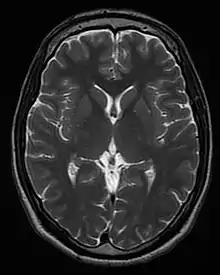

T1 and T2

Each tissue returns to its equilibrium state after excitation by the independent relaxation processes of T1 (spin-lattice; that is, magnetization in the same direction as the static magnetic field) and T2 (spin-spin; transverse to the static magnetic field). To create a T1-weighted image, magnetization is allowed to recover before measuring the MR signal by changing the repetition time (TR). This image weighting is useful for assessing the cerebral cortex, identifying fatty tissue, characterizing focal liver lesions, and in general, obtaining morphological information, as well as for post-contrast imaging. To create a T2-weighted image, magnetization is allowed to decay before measuring the MR signal by changing the echo time (TE). This image weighting is useful for detecting edema and inflammation, revealing white matter lesions, and assessing zonal anatomy in the prostate and uterus.

The standard display of MR images is to represent fluid characteristics in black-and-white images, where different tissues turn out as follows: